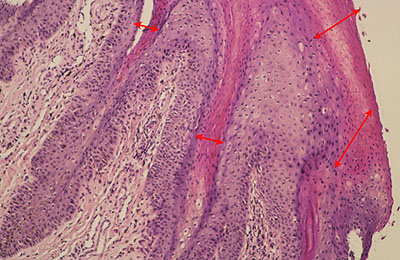

Photo 3 (Hémalun Eosine X 100) : aspect bleu-blanc-rouge à plus fort grossissement,

bleu pour hyperplasie des couches basales, blanc pour vacuolisation des acanthocytes

sous-cornés et rouge pour parakératose de la couche cornée. Le derme superficial est

le siège d’un infiltrat inflammatoire mononucléé périvasculaire modéré.

Légendes de la Photo 3 :

- Flèche bleue pour hyperplasie des couches basales

- Flèche blanche pour vacuolisation des acanthocytes sous-cornés

- Flèche rouge pour parakératose de la couche cornée

- Étoile rouge : Le derme est faiblement à modérément inflammatoire